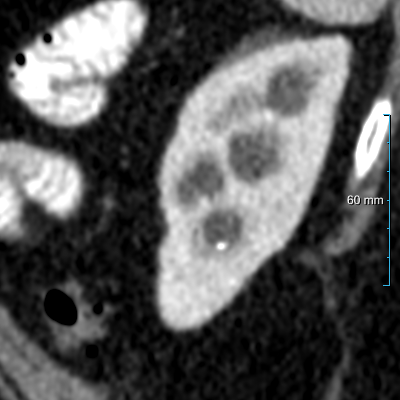

Refer to caption

(a) Input CT scan

(b) Annotations format 1

(c) Annotations format 2

Figure 2: Example illustrating the different annotation formats. Each subfigure shows the same axial section, with overlays depicting the annotations: (a) shows the axial CT section. (b) shows the annotations in format 1: parenchyma and kidney abnormalities as a single structure (yellow overlay). (c) shows the annotations in format 2: parenchyma (yellow overlay) and kidney abnormalities (red overlay) as different structures. All images have a window center of 60 HU and a window width of 360 HU.

This study utilized two annotation formats, format 1 and format 2, to store the annotations. Format 1 considers the kidney parenchyma and kidney abnormalities as a single class (see Figure 2(b)) while format 2 separates them into two classes (see Figure 2(c)).